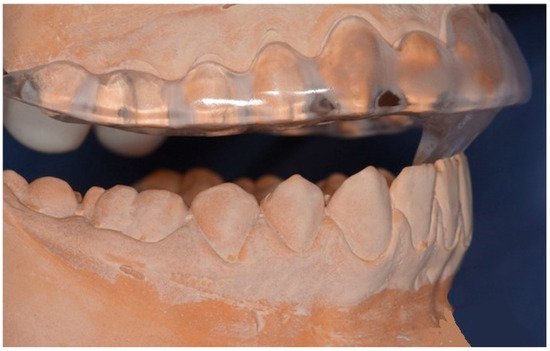

2.6.1. Group 1—MOS Group